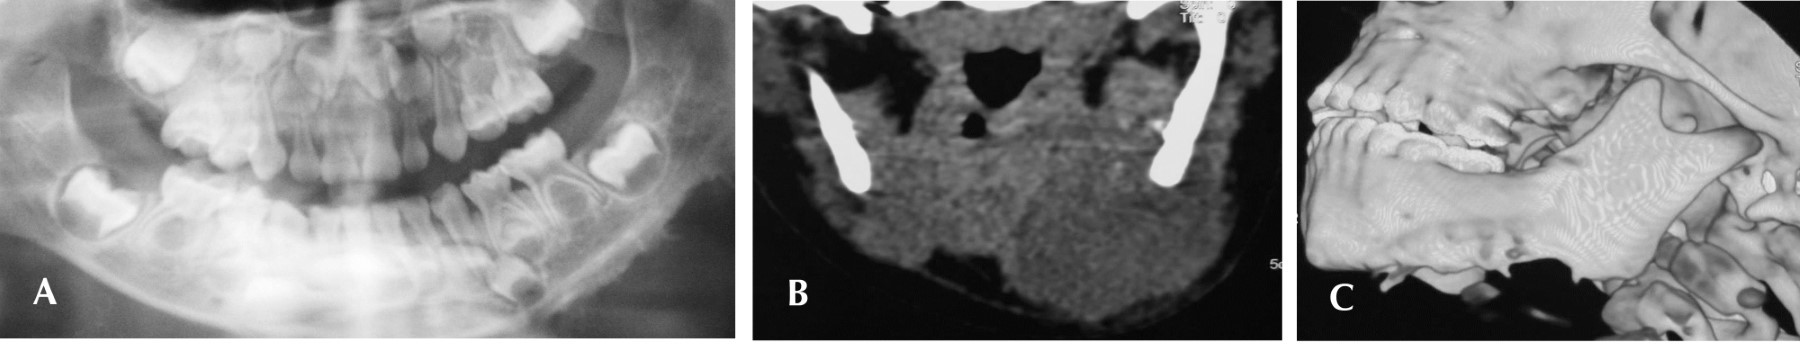

La radiografía panorámica (Figura 2A) evidenció una asimetría a expensas del borde mandibular inferior izquierdo, donde se identificó pérdida de la uniformidad en el contorno óseo cortical, con algunas prolongaciones radiopacas más allá del borde mandibular, sin desplazamiento o afección a los órganos dentales ni al trabeculado del hueso.

Se realiza subsecuentemente una tomografía computarizada simple y contrastada en las cuales se aprecia una lesión unilocular asociada al borde inferior izquierdo de la mandíbula, correspondiente a una masa de tejido blando de 3.15 × 3.27 cm de diámetro aproximado, desplazando el contorno óseo sin llegar a presentar una invasión medular franca e íntimamente relacionado al periostio, asimismo, se vuelven a observar las prolongaciones óseas provenientes de la cortical mandibular hacia la lesión (Figura 2 A y B ).